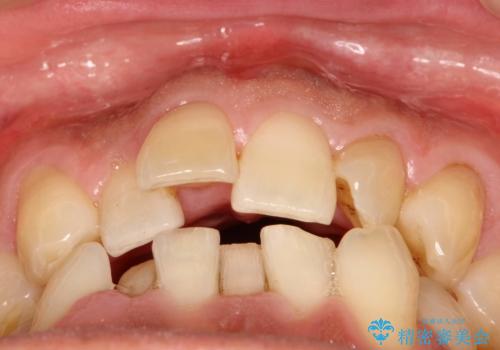

インビザライン invisalign ガタつきを治すマウスピース矯正

- 非抜歯・上顎臼歯遠心移動によるマウスピース矯正を計画した。

ガタつきを取り除くだけであれば非常に簡潔であるマウスピース矯正ですが、奥歯の位置関係の是正や、垂直的な歯の位置のコントロールなどが計画に含まれる場合、治療が難しくなってきます。